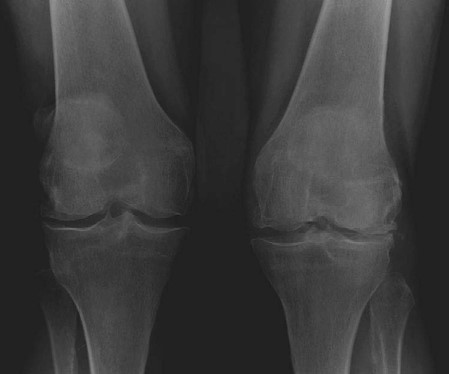

KNEE Structured oral examination question1: TKR in valgus knee EXAMINER : This is a radiograph of a 72-year-o…